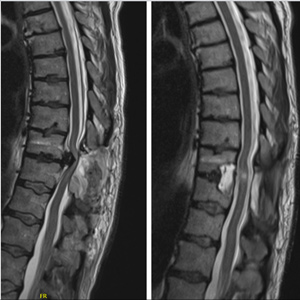

Spinal stenosis (Lumbar) Spinal stenosis (Cervical) Spinal stenosis (Thoracic) Lumbar Disc Herniation Spondylolisthesis Cervical Foraminal Stenosis Vertebroplasty Lumbar Fusion Anterior Cervical Fusion (ACDF) Posterior Cervical Fusion Thoracic Fusion Revision Lumbar Fusion Surgery Facet Joint Cyst Spinal Tumour Minimally Invasive Lumbar Fusion (XLIF) Minimally Invasive Lumbar Fusion (ALIF) Lumbar Fusion (TLIF) Thoraco-lumbar Fusion Lumbar Corpectomy Complex Lumbar Spine Surgery (Spino-pelvic fixation) Complex Cervical Spine Surgery Complex Thoracic Spine Surgery Occipito-cervical Fusion Minimally invasive surgery for thoracic disc herniation Other Related Topics